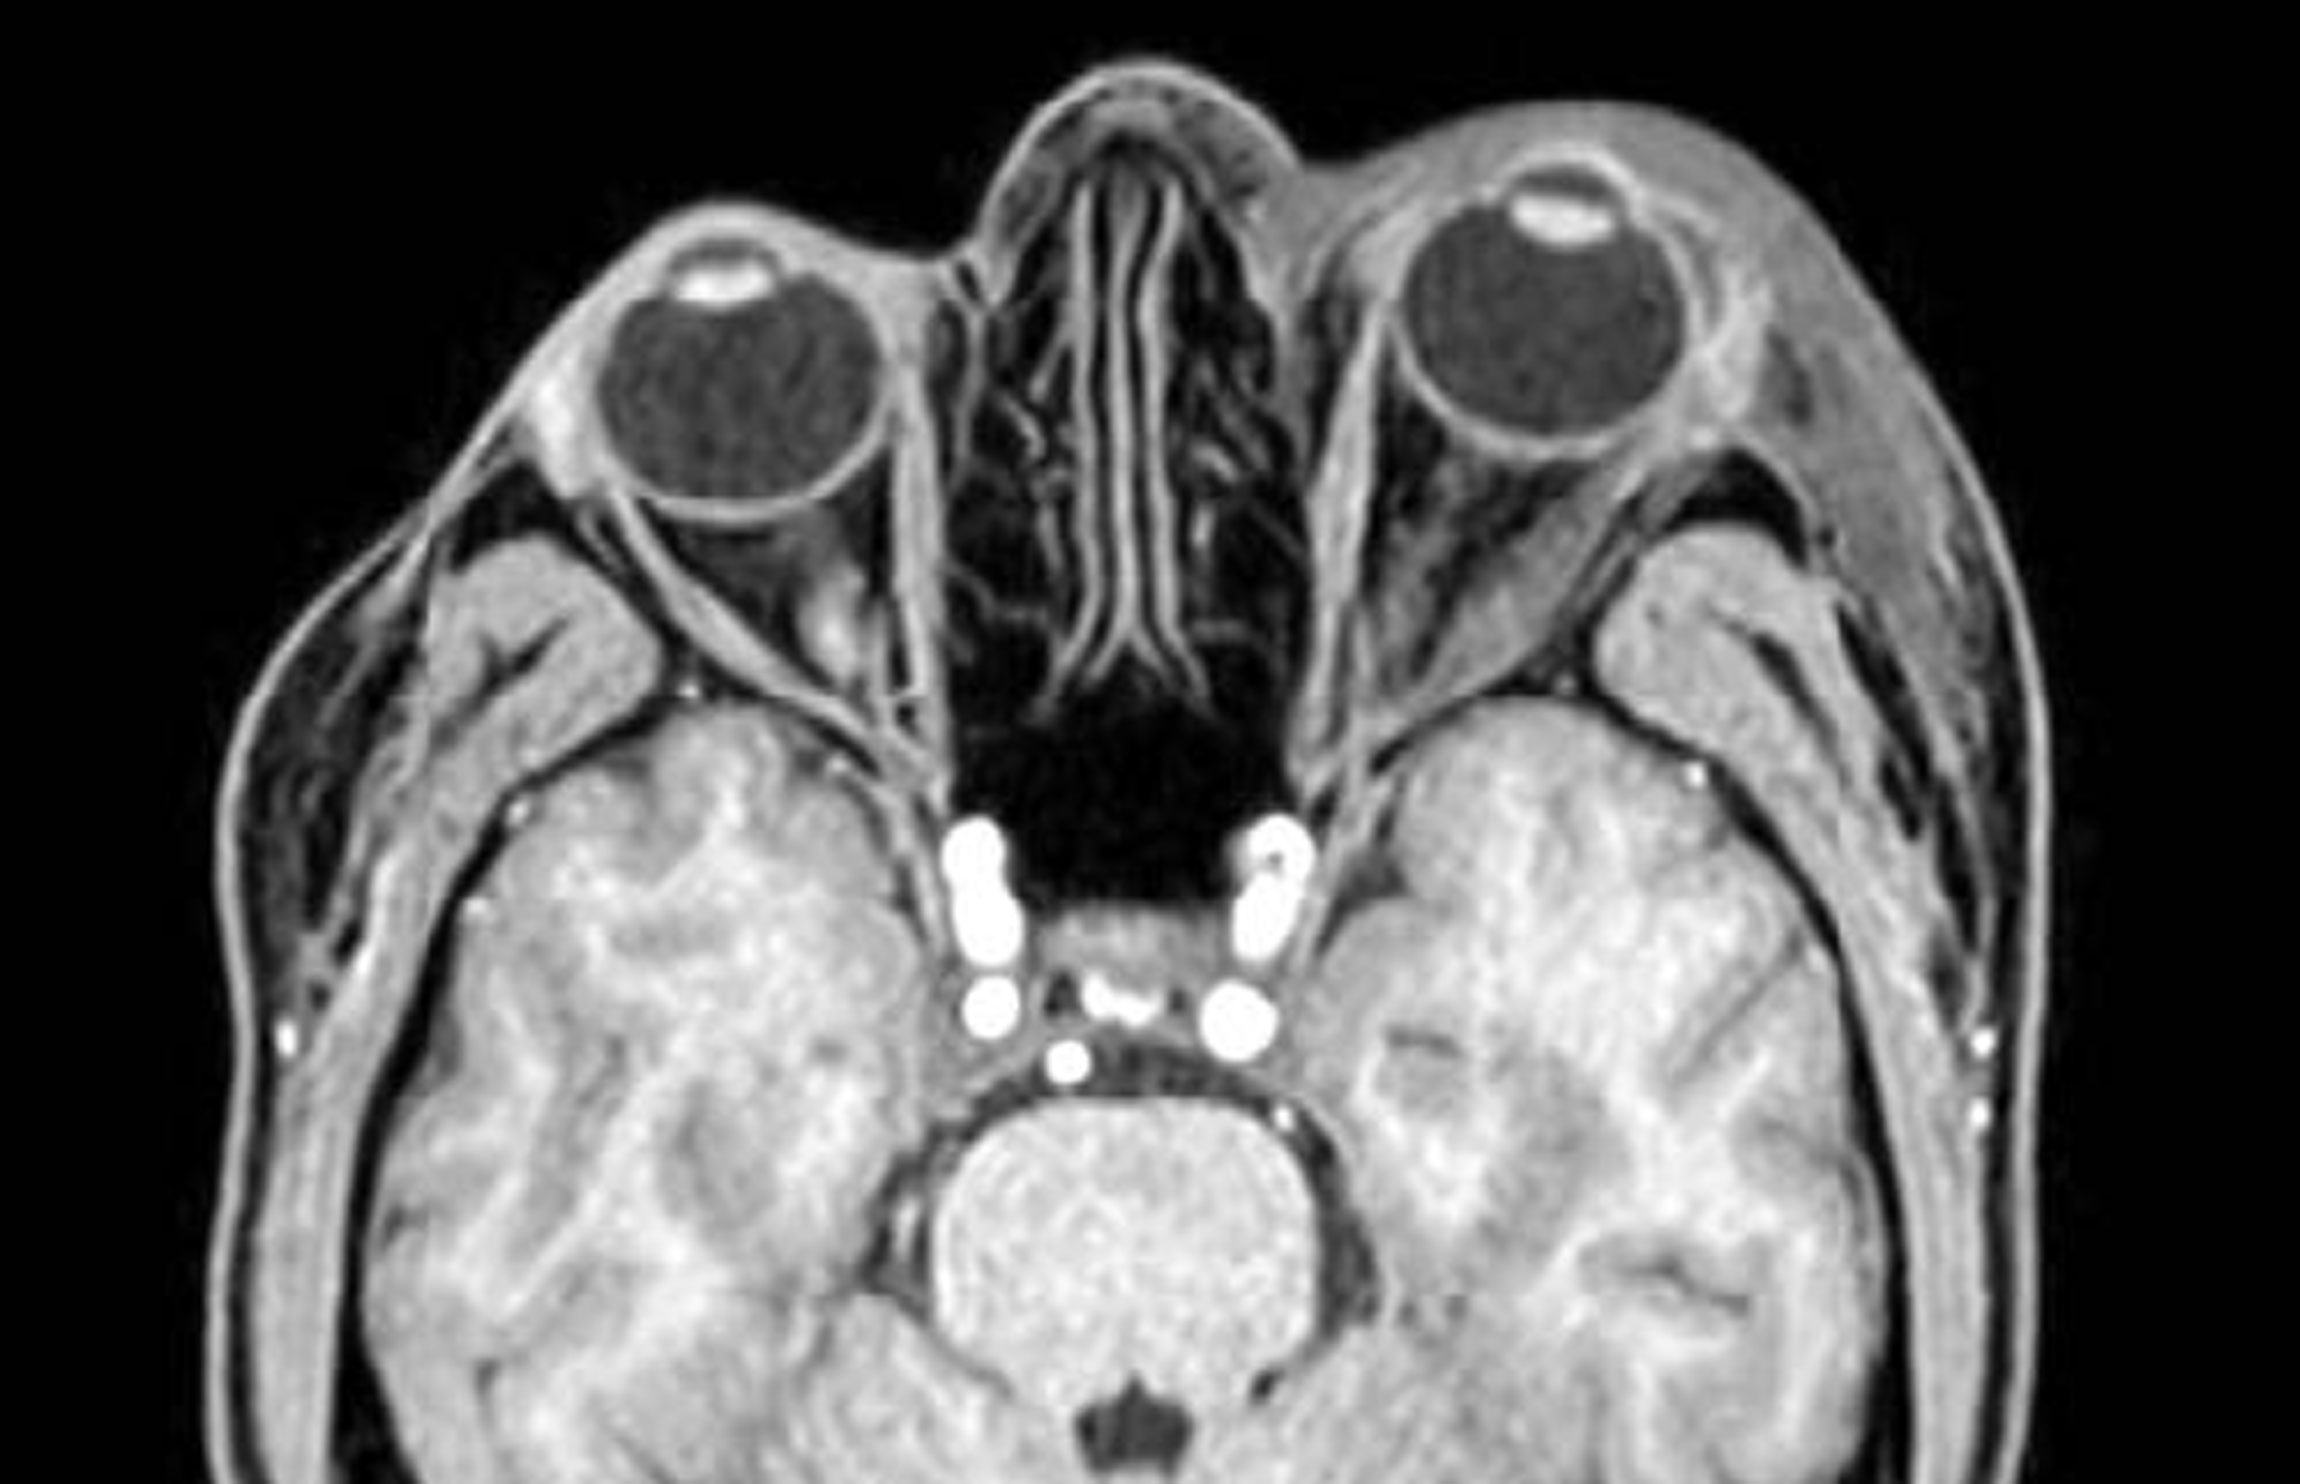

Figure 1. MRI Orbit with contrast both. The scan confirms the presence of significant left-sided proptosis. There is marked oedema of the left lateral rectus muscle but this does not appear to involve the tendinous insertion. There is similar, but less marked oedema of the left superior and inferior rectus muscles. The other extraocular muscles on the left and on the right are normal in appearance. The left lacrimal gland also appears oedematous. There is mild enhancement of the affected extraocular muscles and the left lacrimal gland following IV contrast. Normal appearances of both optic nerves. No evidence of significant intraconal or extraconal mass lesions on either side. The globes are unremarkable in appearance. There is a significant oedema in the skin and subcutaneous tissues around the left orbit.

As seen in Figure 1, MRI orbits confirmed the presence of a significant left-sided proptosis secondary to extraocular muscle and lacrimal gland enlargement. MRI head, MRI cerebral veins, and MRA head were noted to be normal.